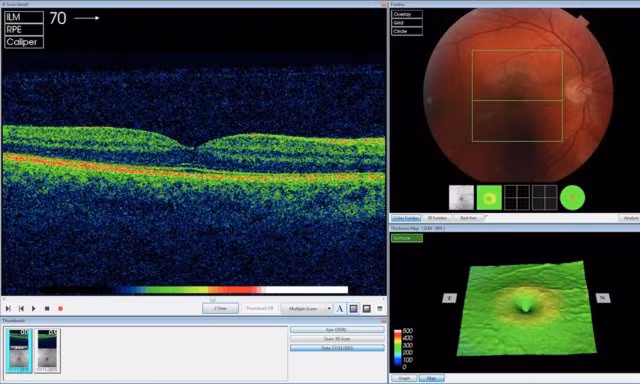

Nói cách khác, AI của DeepMind không giống như một chiếc hộp đen bí mật giúp nhả ra các kết quả. Thiết bị của DeepMind gắn các điểm ảnh lên hình ảnh quét OCT (chụp cắt lớp quang học) mắt để ánh xạ mô mắt và hiển thị các dấu hiệu bệnh cụ thể, từ đó có thể tính toán độ chính xác của những phát hiện và đề xuất của thiết bị trên cơ sở tính số %, ông Suleyman giải thích. “Điều này có ý nghĩa rất lớn”, ông nói thêm.

![]() |

| AI của DeepMind đang phân tích hình ảnh quét OCT (Ảnh DeepMind). |